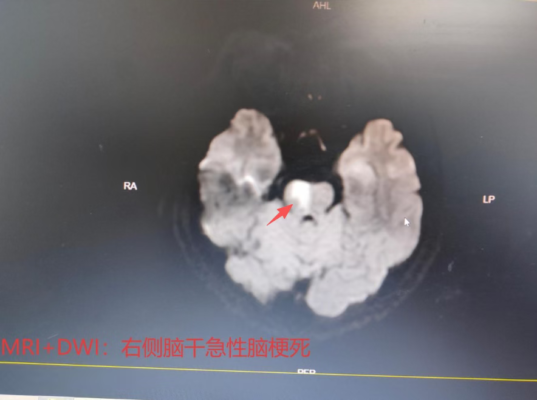

接诊后,急诊科医护人员结合患者症状,怀疑其为急性脑血管意外,当即启动了“卒中救治绿色通道”。为抢抓治疗时机,医护团队在30分钟内高效完成了头颅CT、血常规、生化常规等一系列关键检查。CT结果排除了脑出血可能,明确诊断为急性脑梗死。此时,距离静脉溶栓时间窗仅剩1小时。

术中,脑血管造影清晰显示,患者大脑基底动脉穿支血栓形成,这正是其突发不适症状的直接原因。面对复杂的血管病变,经验丰富的介入科团队沉着处置,在椎动脉内精准给予替罗非班注射液进行动脉抗血栓治疗。治疗10分钟后,堵塞的血管成功再通。随着脑部血流恢复,患者的头晕症状明显改善,四肢活动也逐渐恢复正常,与发病前状态一致。